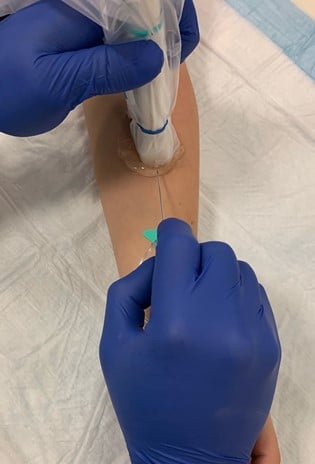

- Needle advances in the vessel (Fig. 7)

Figure 7. Long axis approach: entering the vessel